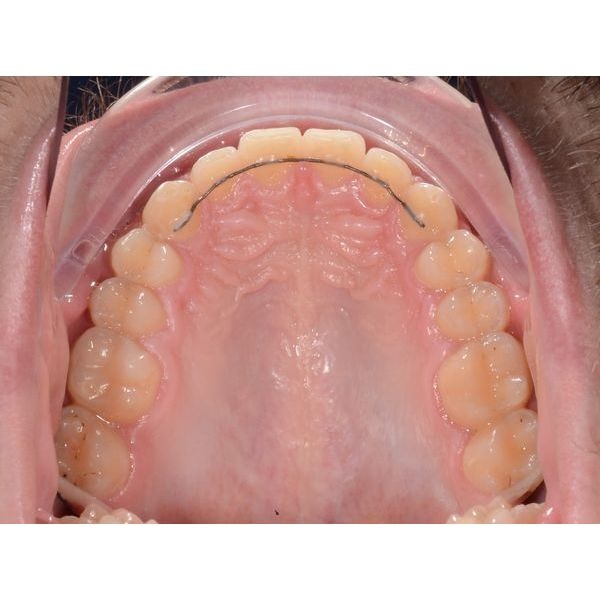

Чтобы сохранить результат, пациенту установили несъёмные ретейнеры (проволочные конструкции, удерживающие зубы в нужном положении) и изготовили индивидуальную ретенционную капу на верхнюю челюсть. Мужчину проинструктировали по поводу режима ношения и уходу за ретенционными аппаратами.